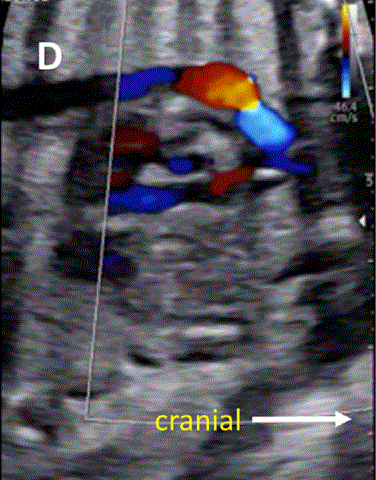

• 评估肺动脉瓣流量和通畅性至关重要,因为这种病变可能与解剖性或假性肺动脉闭锁(功能性)有关。后者肺动脉瓣闭锁,是因为 RV 压力比全身压力低有关(图 29)。

图29胎儿Ebstein异常和TV发育不良。(A)在该胎儿中,严重的三尖瓣反流与进行性心脏增大有关,尤其是右心房(RA)扩张,如这些在19周和34周时的系列图像所示,并且可能与心力衰竭/水肿的演变有关。(B-D)四腔切面中胎儿严重Ebstein异常显示严重心脏扩大的图像。(C)从矢状切面可见广泛的三尖瓣反流(箭头),由于室间隔瓣叶移位,反流起源于TV瓣环下方,甚至向 RV 流出道射流。彩色多普勒和 CW 多普勒显示也有连续的肺动脉反流。(D) 后一项发现表明,右心室无法产生足够的压力来打开肺动脉瓣